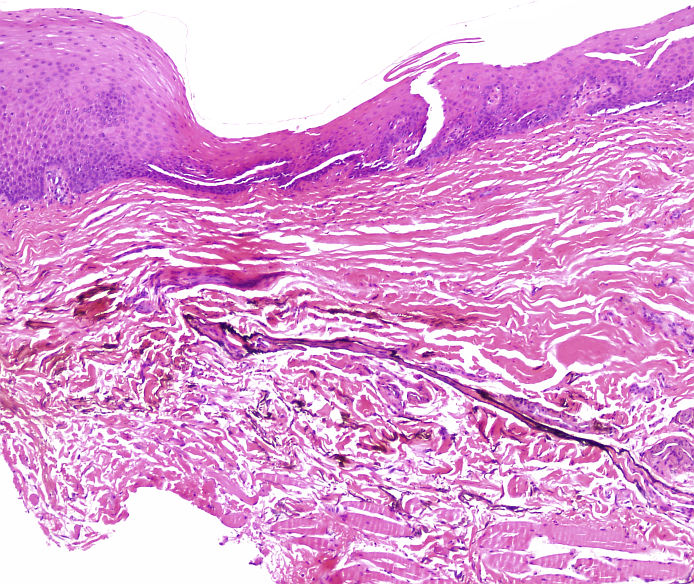

Cas dermatopatologia. Lesió interdigital al peu que supura des de fa setmanes

Abril 2013